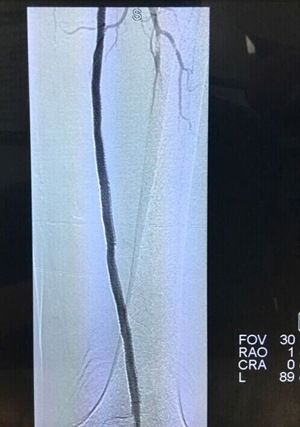

手术前影像图